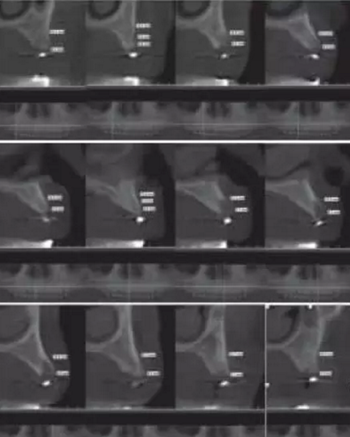

1.2.3治療過程:先行微創(chuàng)拔除14、13、21、22、23、24及25,搔刮拔牙窩去除炎癥組織,常規(guī)制作一副上頜過渡義齒(圖4,5)。2個月拔牙術后復診,利用上頜過渡義齒作為個性化托盤取上頜模型并翻制石膏模型,在石膏模型上根據(jù)過渡義齒標出各個牙位,同時利用壓膜機制作放射性模板(如圖6)。患者佩戴放射性模板拍攝全景片及CBCT(如圖7、8)。

圖8 佩戴放射性模板CBCT